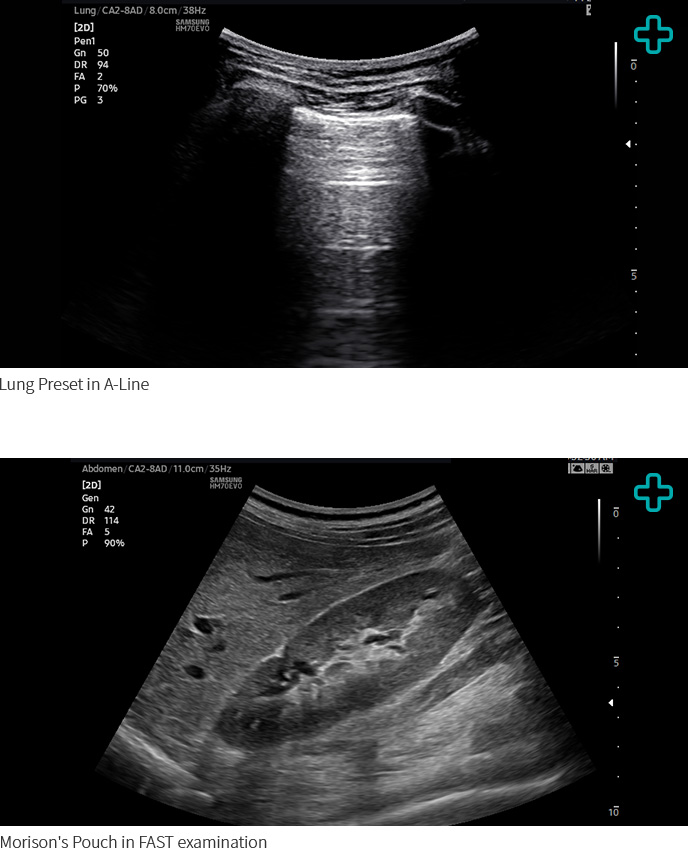

The HM70 EVO supports a wide range of clinical applications, environments, and patient types—including abdomen, cardiac, vascular, musculoskeletal, breast, emergency, and small parts. Especially, HM70 EVO reinforces the EM application with Lung and FAST presets. The versatility enables healthcare professionals to perform effectively on targeted examinations.

Lung Preset in A-Line, Morison's Pouch in FAST examination Lung Preset in A-Line, Morison's Pouch in FAST examination